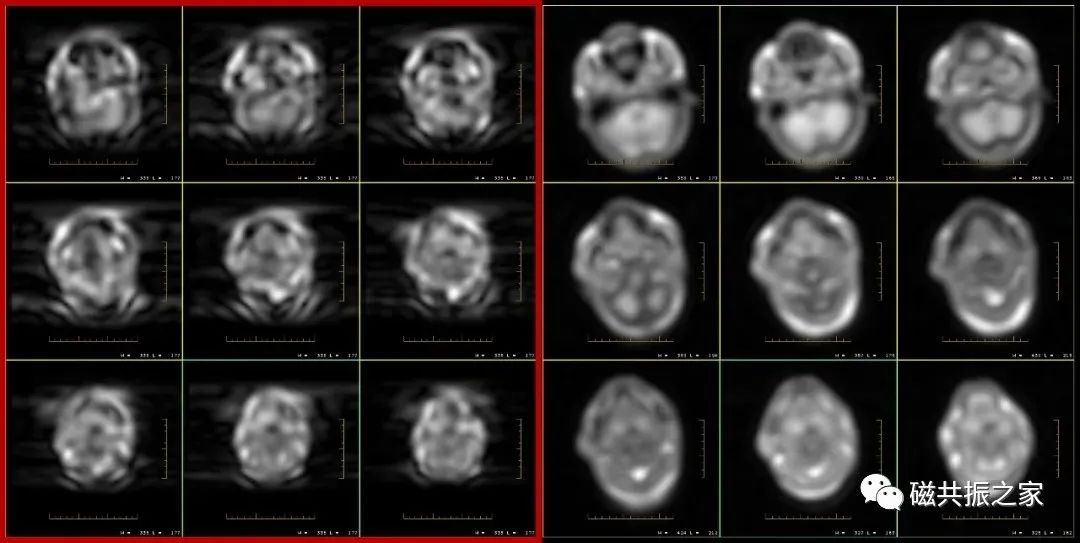

在实际的扫描中,认真翻阅定位像和校准图像的人,可以说是少之又少。但看似毫无用处的校准图像,其能为我们提供一些极其重要的信息。如从上图△,从两组图像中,你能看出什么问题?

在前期的文章中我们曾介绍过使用校准图像来识别伪影的一些问题,本期将介绍有关校准序列的一些其它作用,仅供大家参考。我们知道在MRI成像中为了获得相应的敏感度信息,在其序列扫描前都会先进行预扫描或是校准扫描,这个校准扫描可以是独立的扫描序列,也可以是整合到了相应的扫描序列中(大部分机型已将校准扫描序列整合到了扫描序列中)。不管是何种方式的校准扫描,我们都能从校准图像中获取一些不一样的信息,并通过这些关键性的信息可以对后续扫描做出相应的评估及调整。

校准序列的两组图像:校准扫描通过当前使用的线圈和大磁铁线圈分别扫描获得两组图像,如上图△,当前使用的线圈为8ch body fullfov;大的磁铁线圈为BODY,从图像可以看出BODY扫描的图像信号强度不及8ch body fullfov扫描的图像。在临床扫描中通过观察或对比两组图像的信号差异可以获得一些重要的信息。